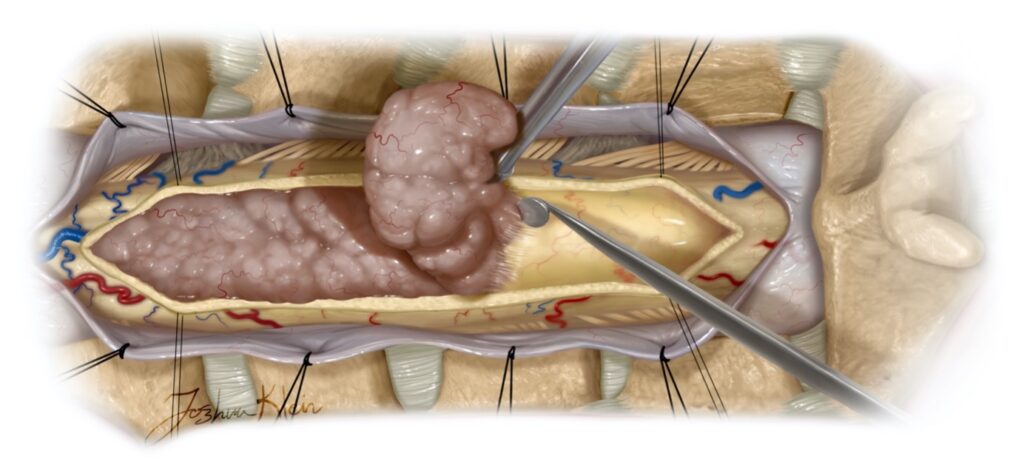

۱. عمل جراحی (تخلیه تومور)

جراحی خط اول درمان برای تومورهای نخاعی است و باید در سریعترین زمان ممکن پس از تشخیص انجام شود؛ زیرا وضعیت عصبی بیمار پیش از عمل، تاثیر مستقیمی بر نتیجه جراحی دارد.

هدف جراح، برداشتن حداکثری تومور بدون آسیب رساندن به بافت سالم نخاع است.

-

در تومورهایی مانند اپندیموما که مرز مشخصی با نخاع دارند، امکان تخلیه کامل تومور بسیار بالاست.

-

در تومورهایی مانند آستروسیتوما که در بافت سالم نفوذ کردهاند، جراح معمولاً تنها بخش ایمن تومور را برمیدارد تا بیمار دچار فلج دائمی نشود.

در طول عمل، از دستگاههای مانیتورینگ عصبی استفاده میشود تا کوچکترین تغییرات در عملکرد نخاع به صورت لحظهای بررسی شود.